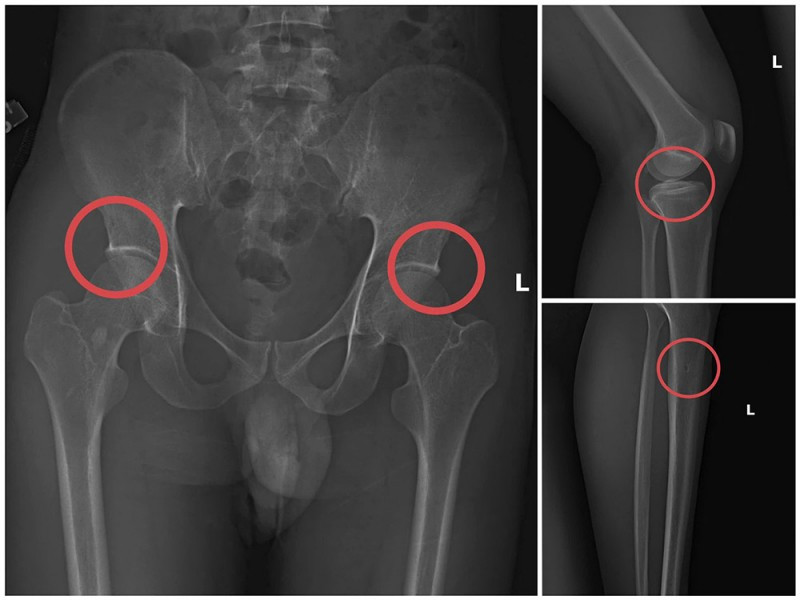

Phim chụp XQ một số tổn thương xương do đối tượng Tạ Minh Châu tạo ra.

Tại đây, Châu tiêm thuốc mê vào tĩnh mạch tay phải của người mua bảo hiểm. Khoảng 1 phút sau khi đối tượng mê đi, Châu dùng búa và kim tiêm đục, đâm vào vị trí đã thống nhất để tạo tổn thương xương (thường là làm rạn nứt hoặc vỡ xương chậu, xương đùi…).